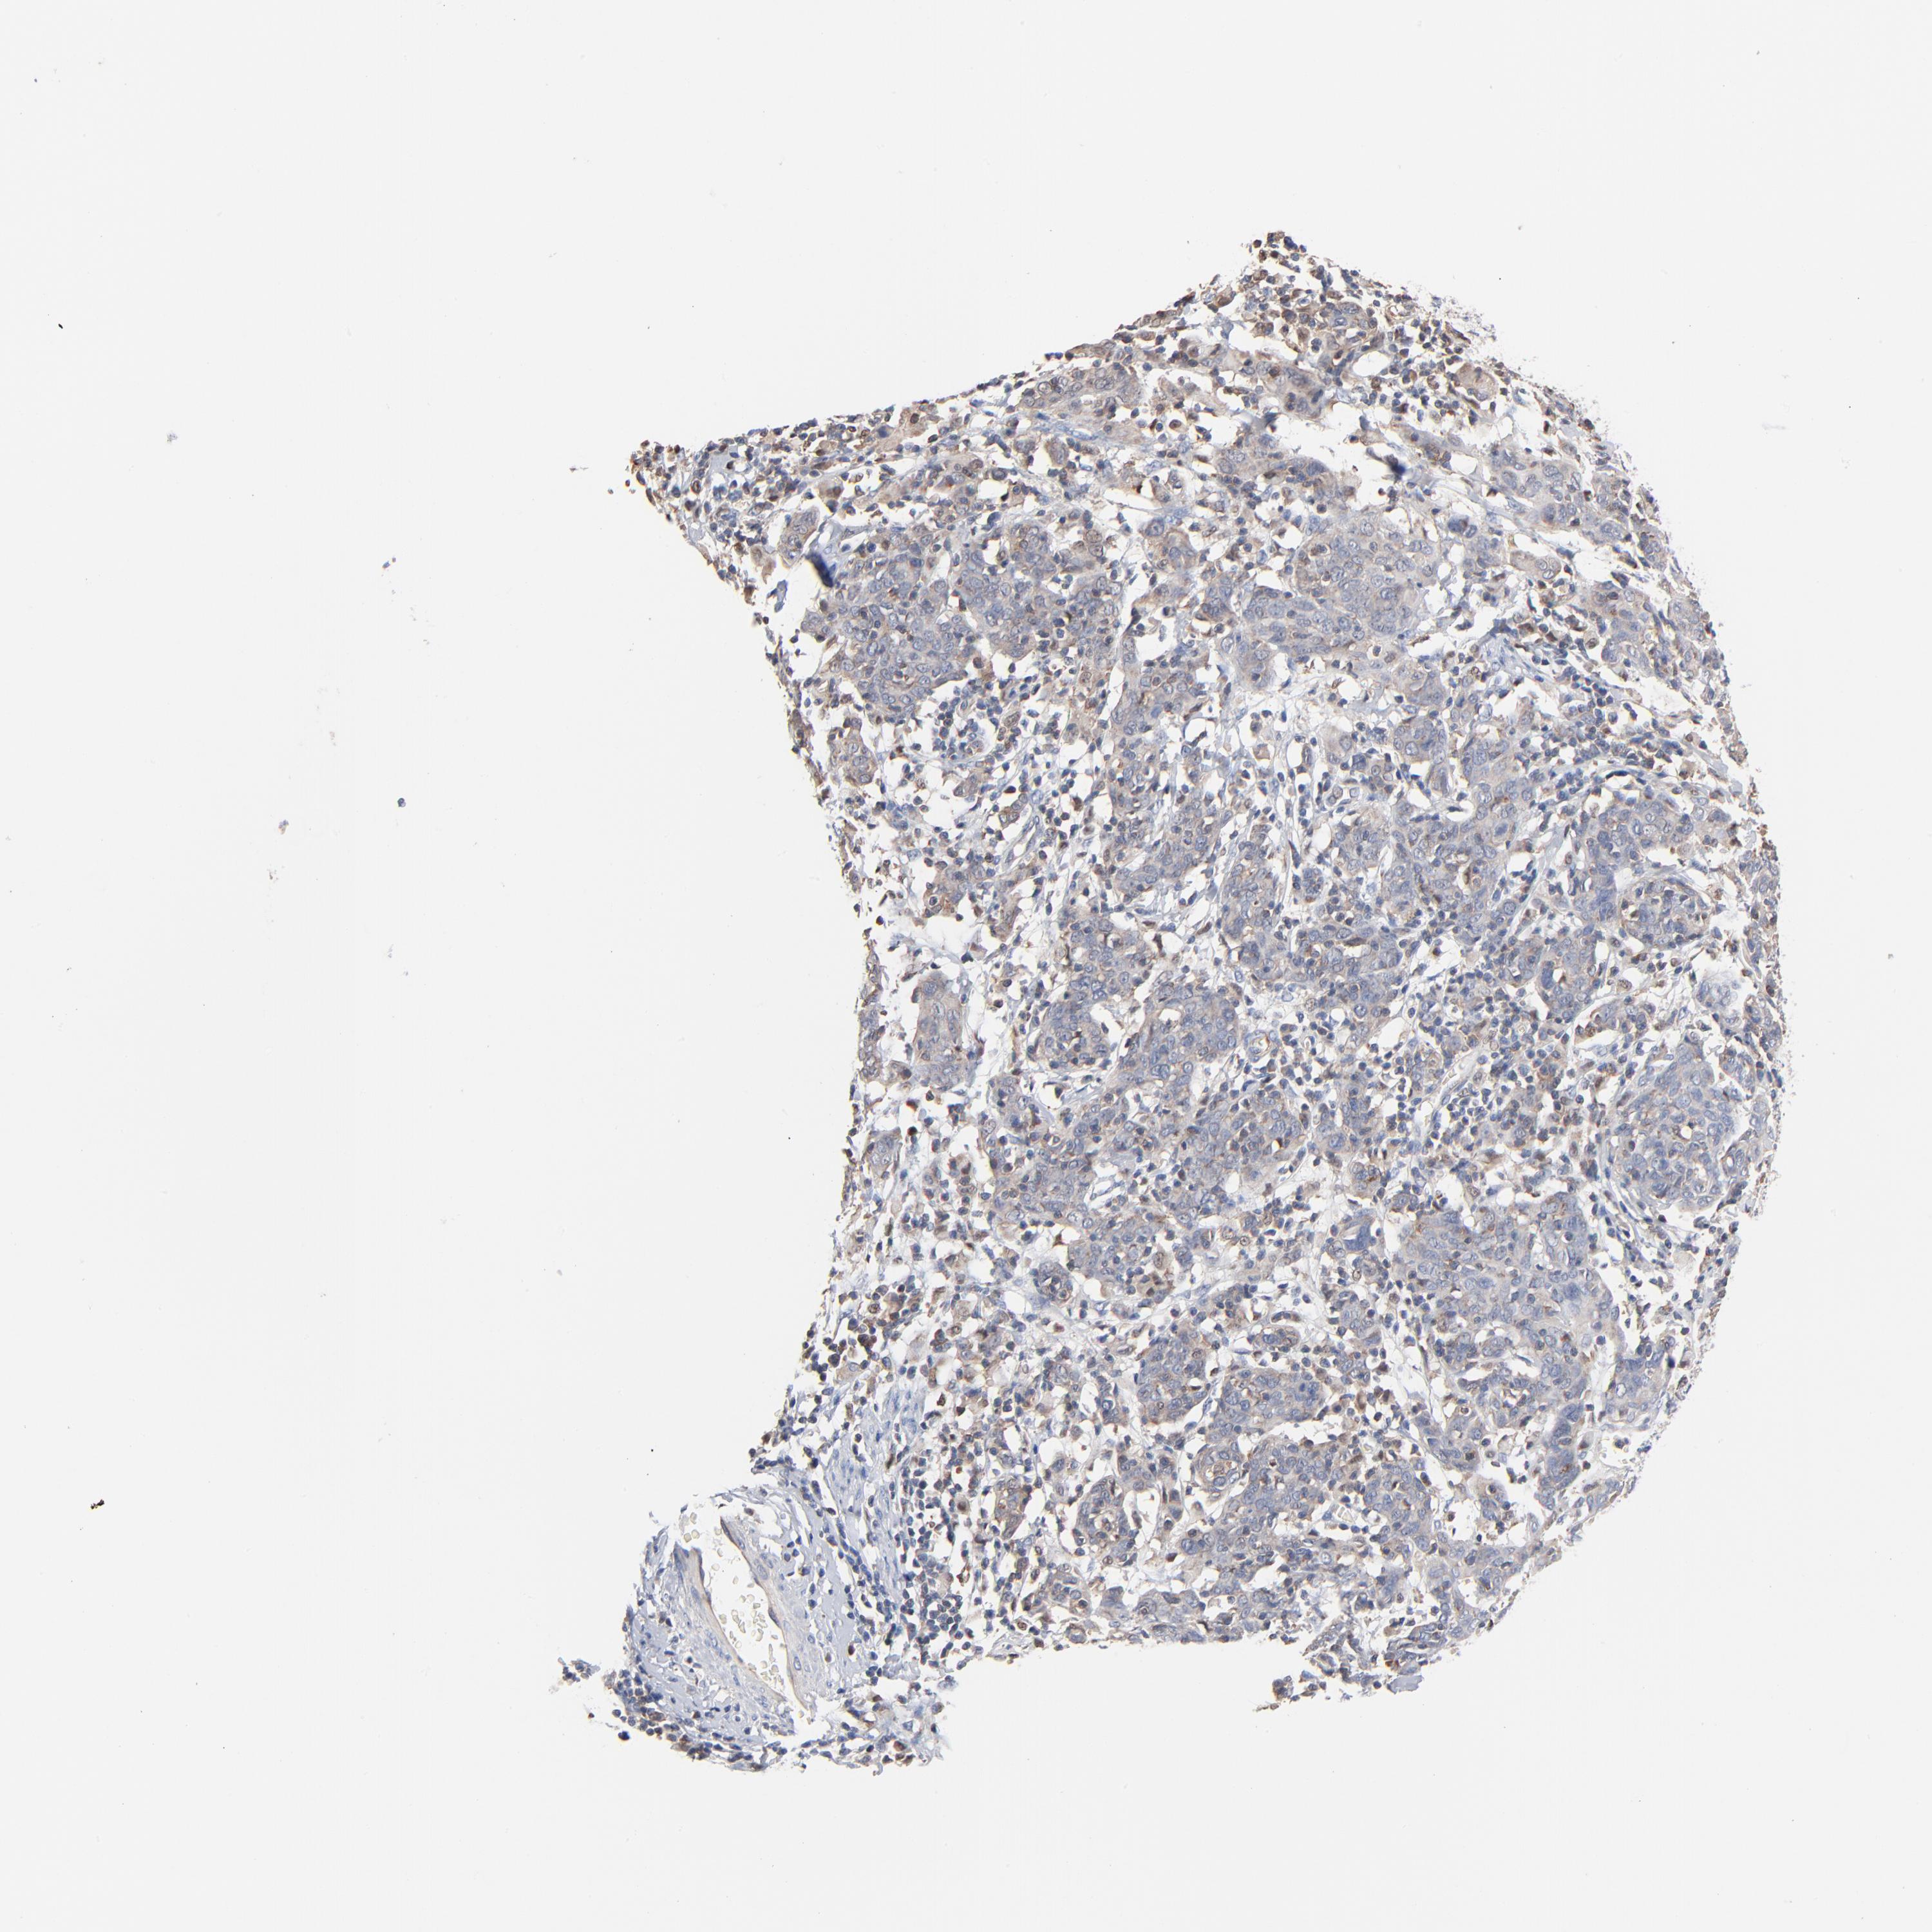

CERVICAL CANCER - Protein expressioni

A mouse-over function shows sample information and annotation data. Click on an image to view it in a full screen mode. Samples can be filtered based on level of antibody staining by selecting one or several of the following categories: high, medium, low and not detected. The assay and annotation is described here.

Note that samples used for immunohistochemistry by the Human Protein Atlas do not correspond to samples in the TCGA dataset.

Antibody stainingi

Antibody staining in the annotated cell types in the current human tissue is reported as not detected, low, medium, or high, based on conventional immunohistochemistry profiling in selected tissues. This score is based on the combination of the staining intensity and fraction of stained cells.

Each image is clickable and will lead to virtual microscopy that enables deeper exploration of all samples and also displays staining intensity scores, fraction scores and subcellular localization as well as patient and tissue information for each sample.

Antibody HPA003578

Staining

High

Medium

Low

Not detected

Intensity

Strong

Moderate

Weak

Negative

Quantity

>75%

75%-25%

<25%

None

Location

Nuclear

Cytoplasmic/membranous

Cytoplasmic/membranous,nuclear

Squamous cell carcinoma, NOS